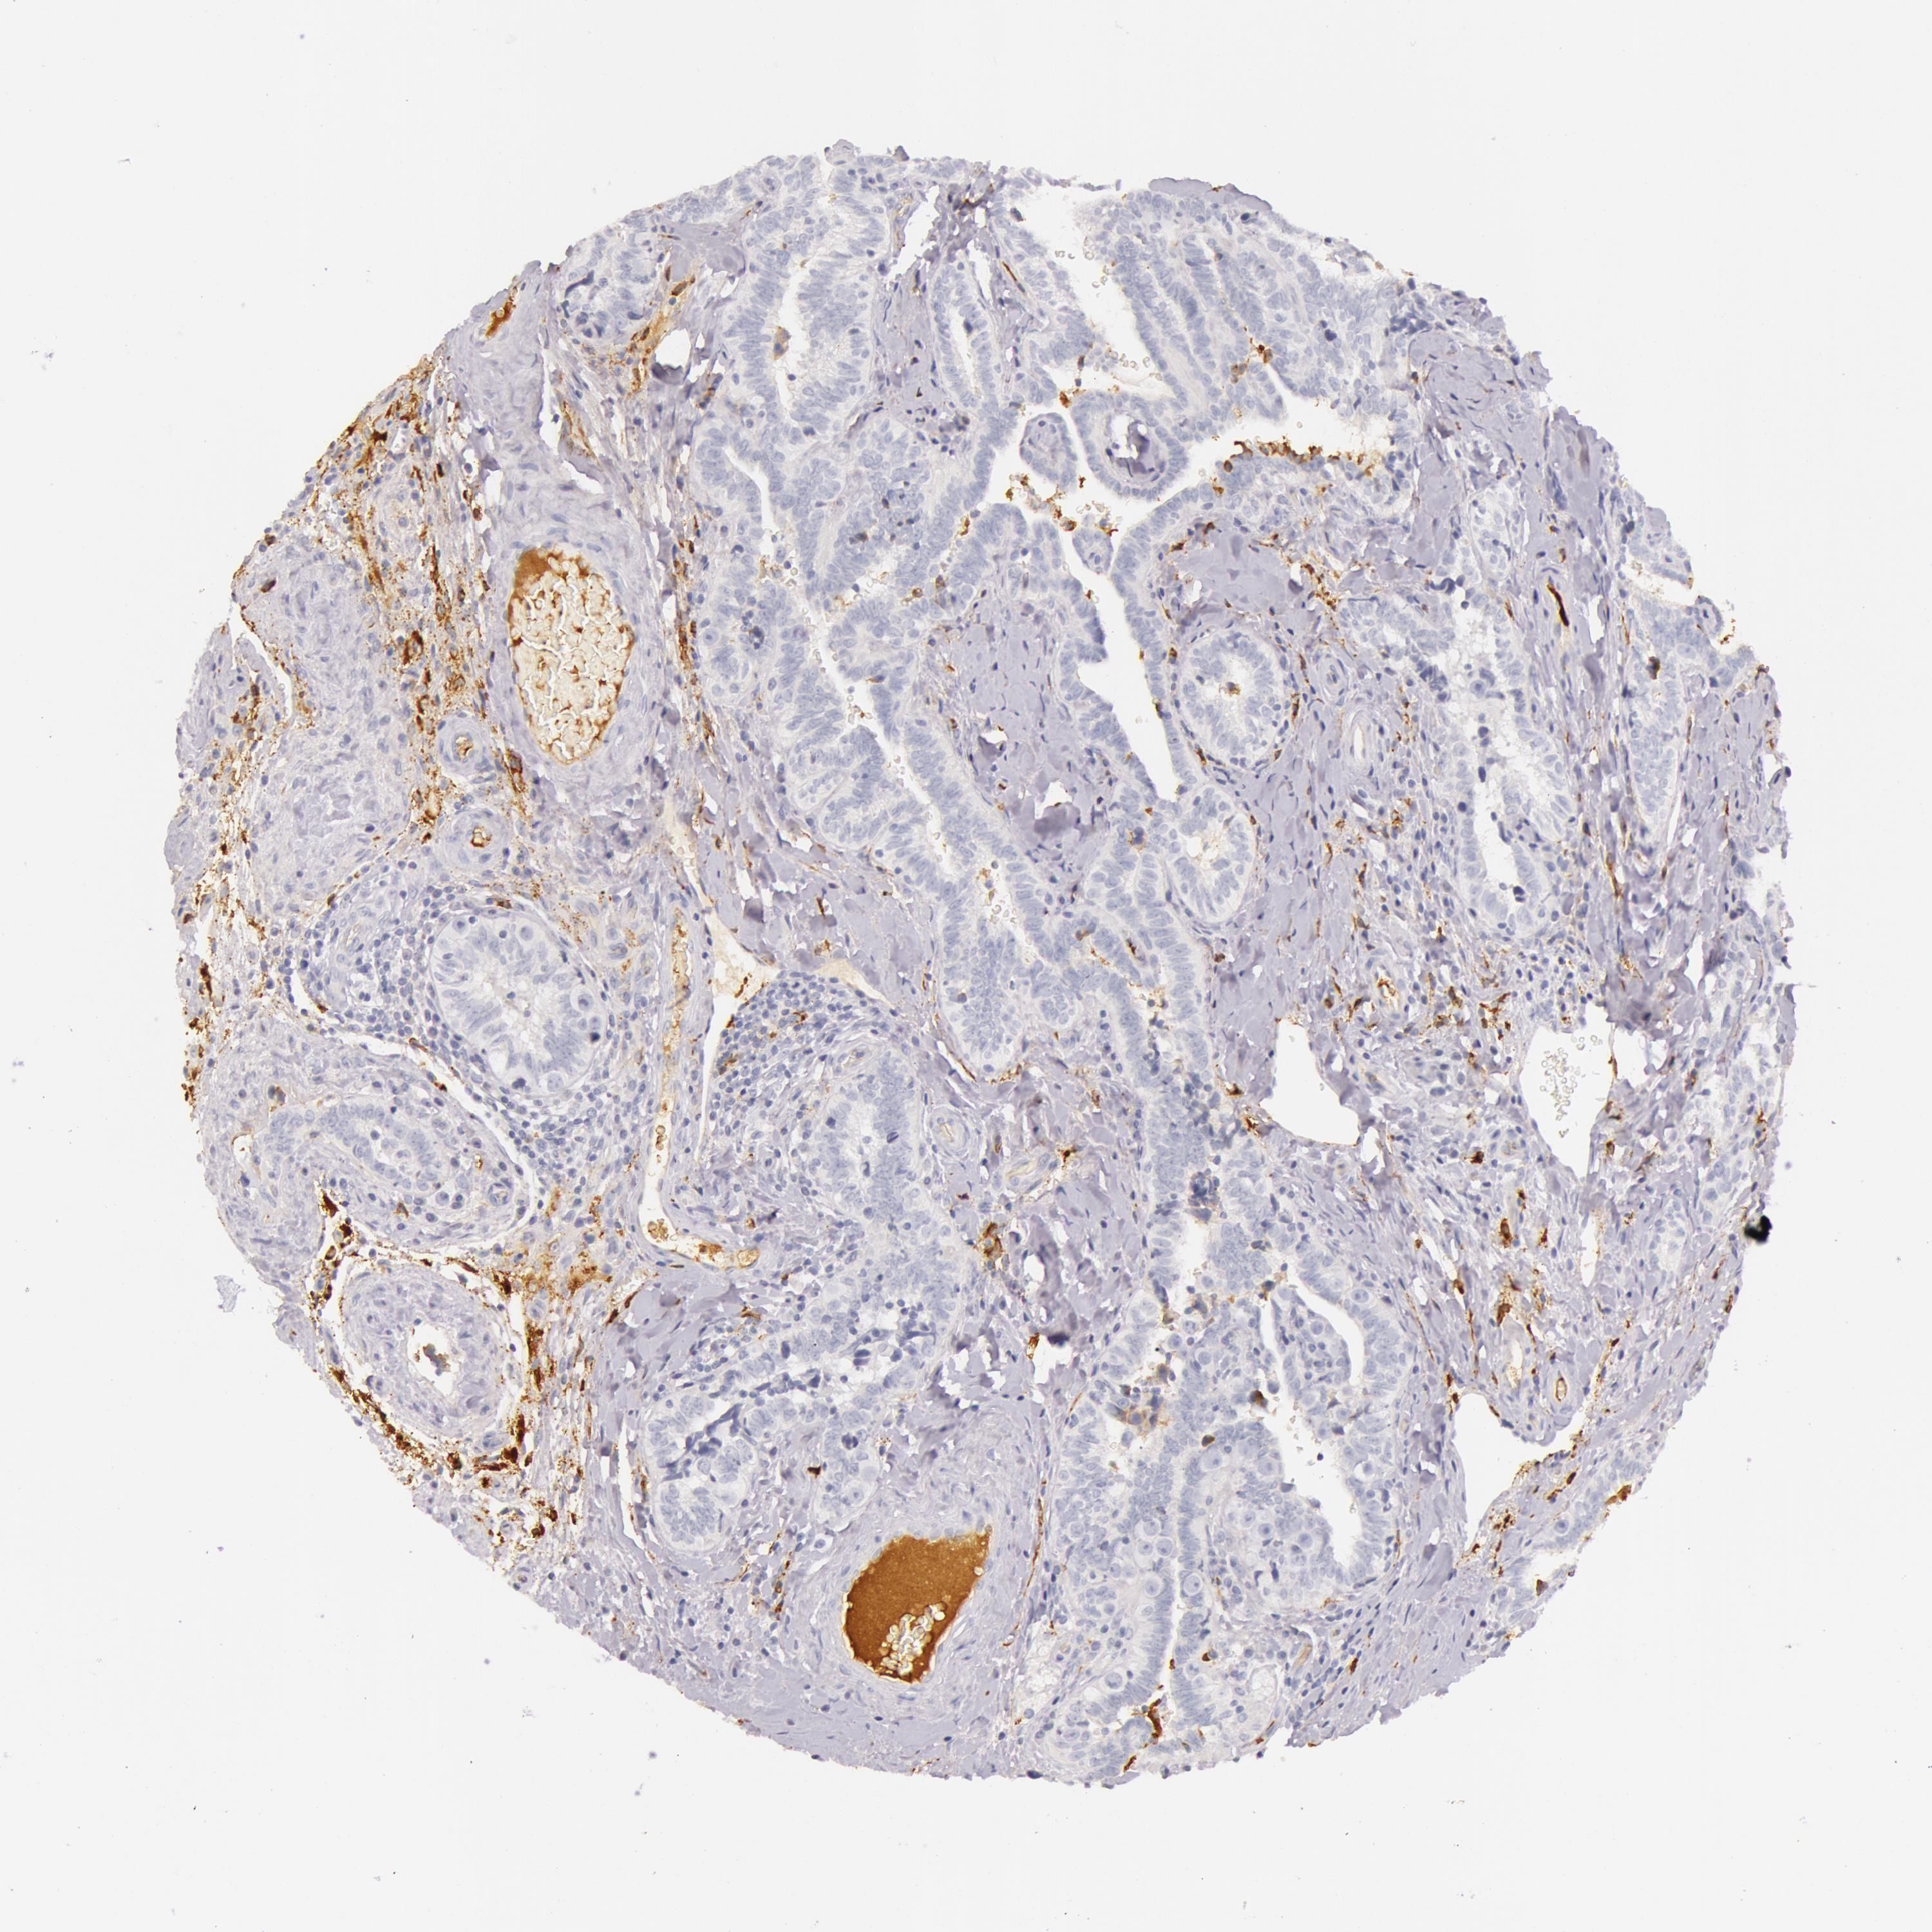

TESTIS CANCER - Protein expressioni

A mouse-over function shows sample information and annotation data. Click on an image to view it in a full screen mode. Samples can be filtered based on level of antibody staining by selecting one or several of the following categories: high, medium, low and not detected. The assay and annotation is described here.

Note that samples used for immunohistochemistry by the Human Protein Atlas do not correspond to samples in the TCGA dataset.

Antibody stainingi

Antibody staining in the annotated cell types in the current human tissue is reported as not detected, low, medium, or high, based on conventional immunohistochemistry profiling in selected tissues. This score is based on the combination of the staining intensity and fraction of stained cells.

Each image is clickable and will lead to virtual microscopy that enables deeper exploration of all samples and also displays staining intensity scores, fraction scores and subcellular localization as well as patient and tissue information for each sample.

Antibody HPA001578

Seminoma, NOS

Carcinoma, Embryonal, NOS